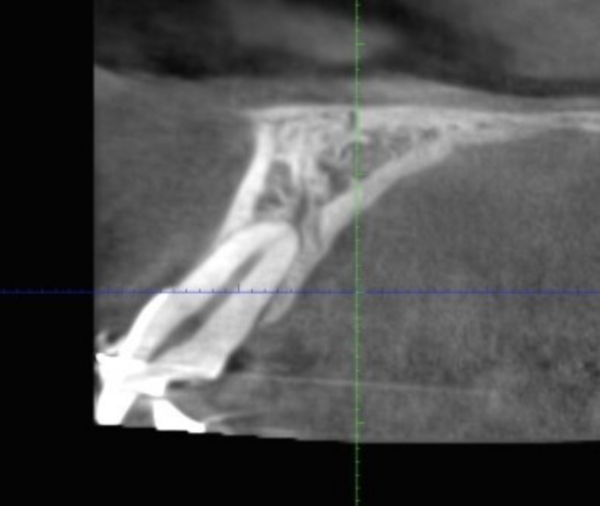

Traitement réalisé chez une jeune femme de 21ans qui présentait une béance antérieure. Le traitement a permis la fermeture de la béance et le redressement de...